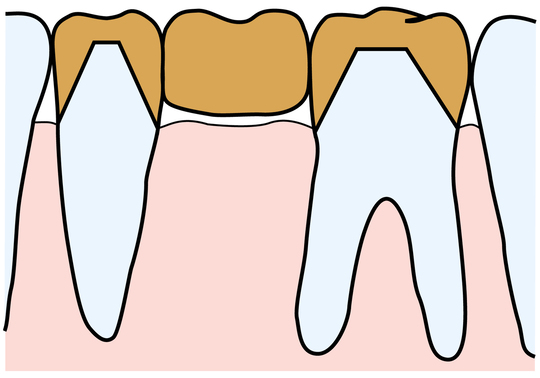

虫歯で歯が割れて周囲に強い歯周病

親知らずを移植し根管治療中

※現在治癒を経過観察中

親知らずを抜歯箇所に移植するのは、他の3つの方法に比べて制限はあるものの、歯根膜を得ることができるということで大きな意味があります。また、前後の歯を削ったり、負荷をかけるブリッジや入れ歯に代わる方法として保険が利くのも魅力です。(保険がきかない場合もあります)予後が読みにくく、多少不確定要素もありますが、上記3つの方法加えて、第4の方法となります。

当院では、安易な親知らずの抜歯を避け、いざという時に移植に使える可能性を残しています。また、移植という高度な歯科医療をしっかり行える体制も整えています。